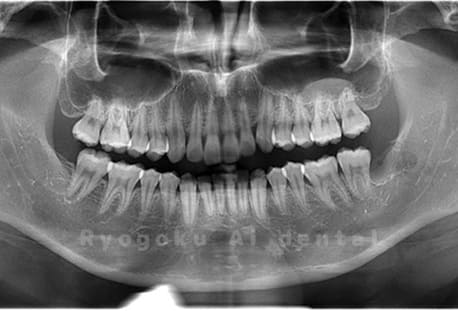

Case01

- 原因

- 水平埋伏智歯

- 治療内容

- 下顎の水平埋伏智歯を抜歯

<リスク・副作用>

手術後は痛み、腫れ、痺れなどの副作用が生じる場合があります。